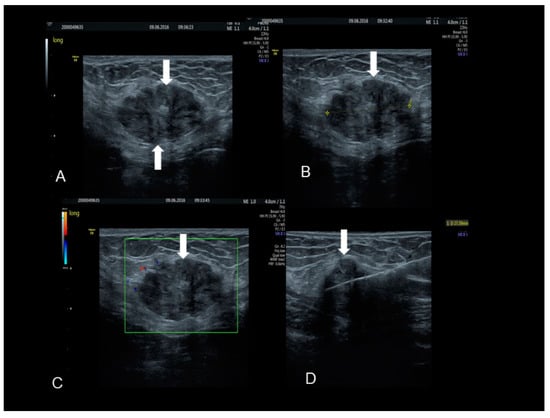

Figure 4. The ultrasonographic appearance of a Villar’s nodule (see white arrows) using B-mode (A) and color Doppler (B,C) with some color spots due to peripheral vascularization in a woman without previous abdominal surgery. In this case the ultrasonographic appearance was more cystic than solid (AC). The nodule at visual evaluation (D).

Villar’s nodule is characterized by the presence of endometrial tissue in the umbilicus as a result of tissue seeding during surgery (Figure 3, Figure 4 and Figure 5). It is a rare condition and it is iatrogenic in the vast majority of cases, correlated to previous abdominal/uterine surgery, although there have been very few reports of umbilical endometriosis without a history of previous pelvic surgery (Figure 3) [17].

This site of extra-genital endometriosis was reported for the first time by Villar in 1886 and since then about 100 cases have been described in the literature. It represents about 0.5–1% of all extra-pelvic locations of endometriosis [18]. Umbilical endometriosis usually appears in patients of reproductive age as a solitary lesion, in the absence of concomitant pelvic locations of disease, unlike other types of endometriosis [18]. From a morphological point of view it presents as a small bluish-pink mass, with a diameter ranging from a few millimeters up to 6 cm, a tendency to swell and cause painful symptoms, particularly in the premenstrual period, and possibly bleeding through the skin covering the umbilicus during menses, earning the title of “menstruating tumor”(Figure 3, Figure 4 and Figure 5).

This umbilical endometriosis may appear as solid areas with ill-defined margins (Figure 3, Figure 4 and Figure 5) that can be irregular or spiculated [11], but more frequently than other endometriotic lesions they may have a cystic appearance (although Nuck nodules may also have this appearance) [18] (Figure 3, Figure 4 and Figure 5). In fact, the typical US finding is a nodular formation that occupies the umbilical scar, with ground-glass echogenicity, irregular margins, and no papillary structures with a detectable blood flow [7]. The absence of continuity with the deep fascial plane allows its differential diagnosis from invasive malignancies and hernias [18].